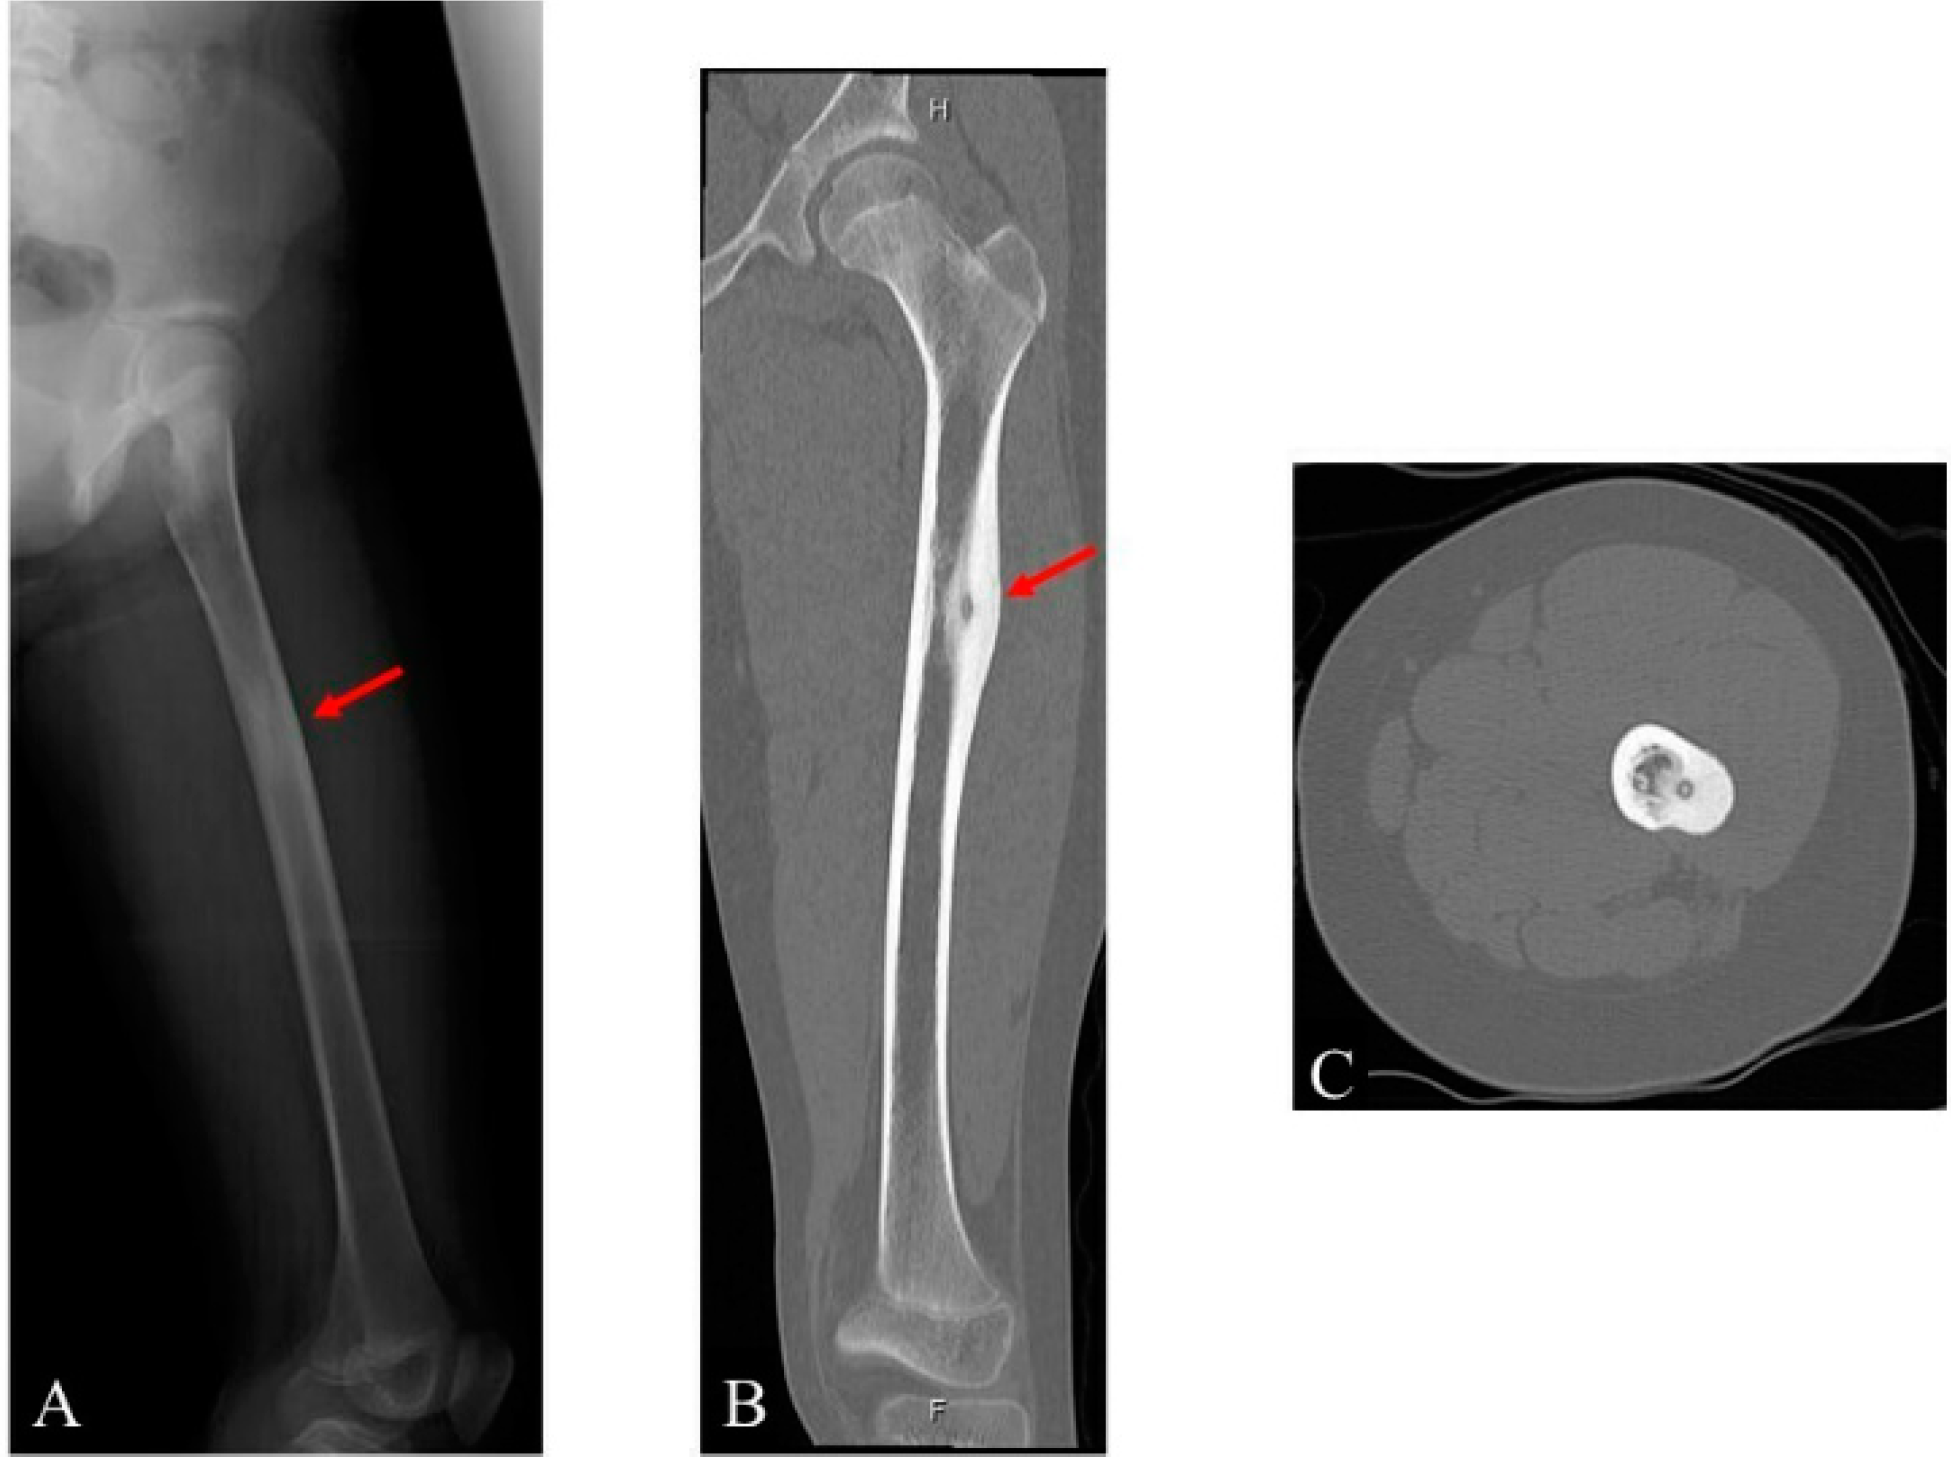

2. Case Presentation

- Clinical and radiological evaluation of the osteoid osteoma.